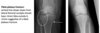

**Colles - ‘dinner fork type deformity’** Features of the injury 1. Transverse fracture of the radius 2. 1 inch proximal to the radio-carpal joint 3. Dorsal displacement and angulation of the distal radius

**Smith's fracture (reverse Colles' fracture)** 1. Volar angulation of distal radius fragment (Garden spade deformity) 2. Caused by falling backwards onto the palm of an outstretched hand or falling with wrists flexed

Colles fracture ## Footnote Typically FOOSH forwards Extra-articular radial # with dorsal (posterior / back of hand) angulation and displacement

Smith Fracture ## Footnote Typically FOOSH back of hand Extra-articular radial # with volar (anterior / palmar) angulation and displacement